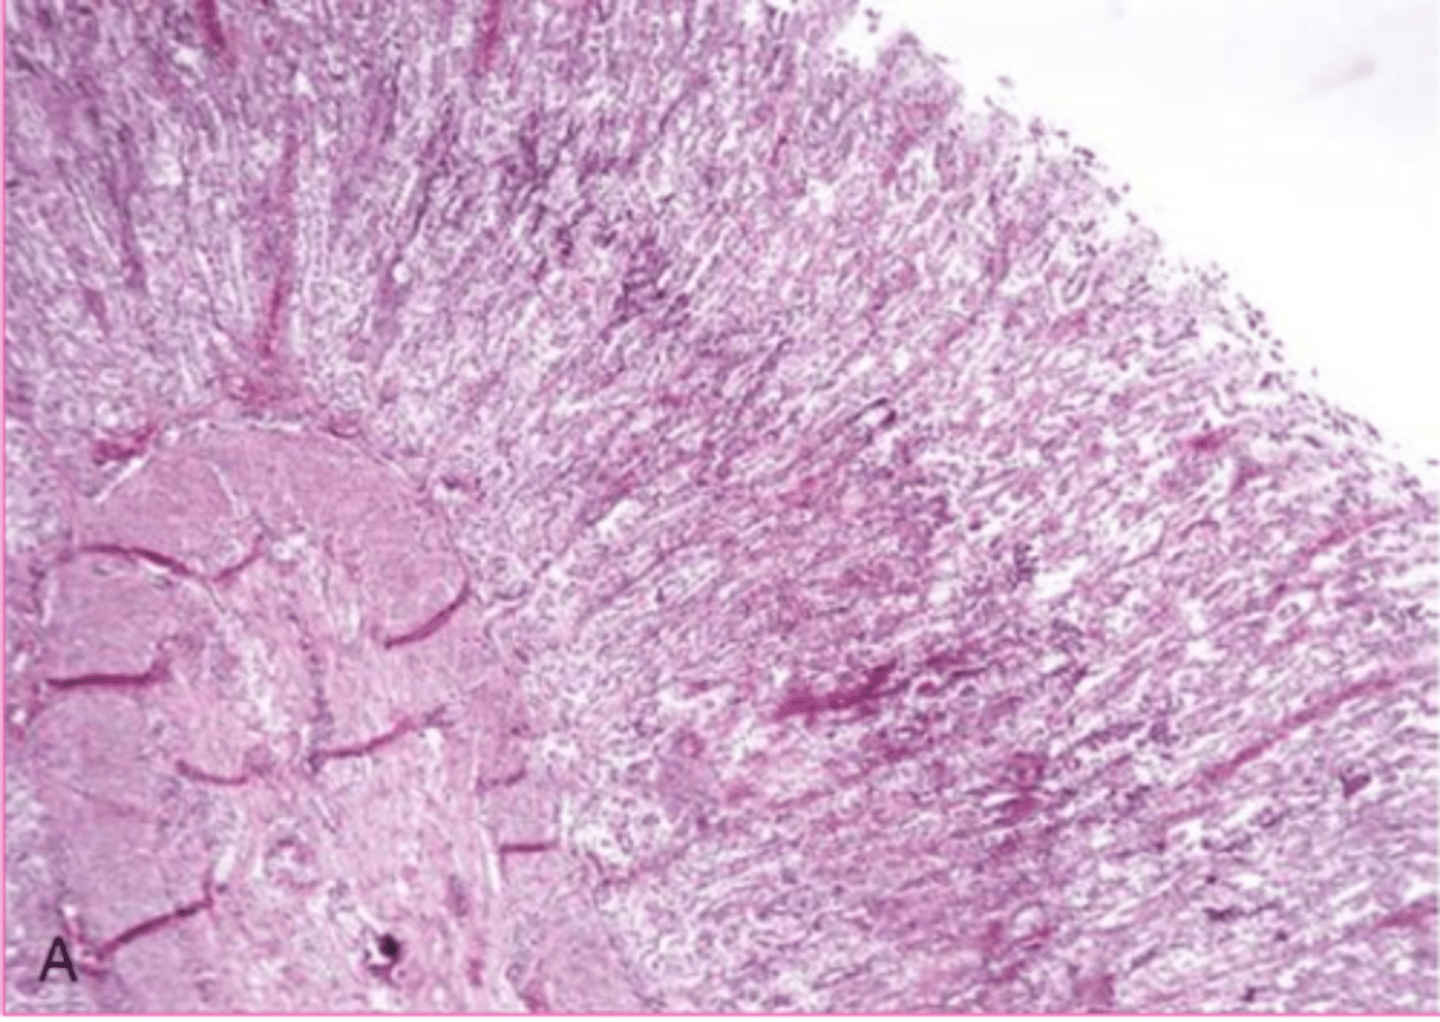

Dural ossification

What is this extracellular accumulation of the dura mater?